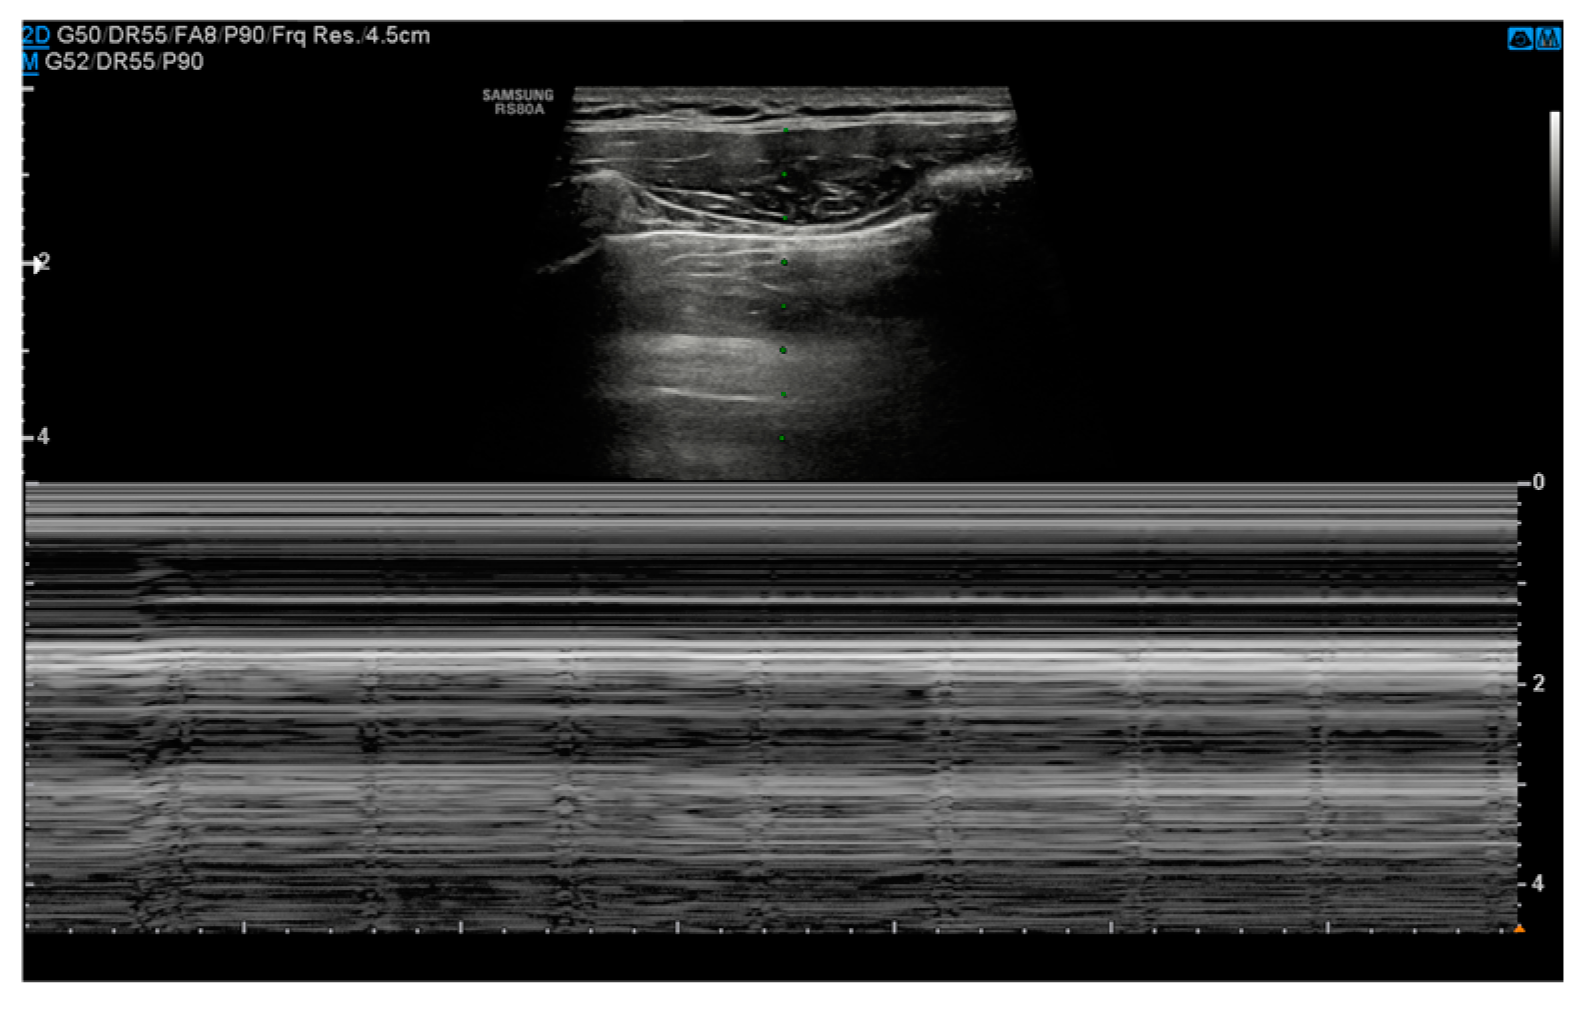

3.2. Ultrasound

- Absence of pleural sliding: Normally, the visceral pleura glides against the parietal pleura with respiration. In pneumothorax, this movement is absent;

- Absence of B-lines: Comet-tail artifacts (B-lines) are reverberation anomalies that disappear with the presence of air in the pleural space;

- Lung point sign: The point where normal lung sliding meets the absent sliding of the pneumothorax; this is highly specific for pneumothoraces;

- Barcode or stratosphere sign: A static, uniform appearance on M-mode ultrasound indicating loss of lung movement (Figure 3).